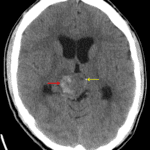

Age: 17

Sex: Male

Indication: Diplopia

CT

Teratoma (pineal region)